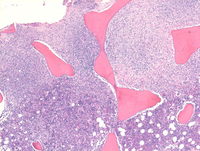

CHL involving marrow low power

Low power image of bone marrow core biopsy demonstrating extensive involvement by Hodgkin lymphoma involving the top half of the image in the biopsy. Normally, there is marked architectural distortion in the bone marrow when there is involvement by classical Hodgkin lymphoma.